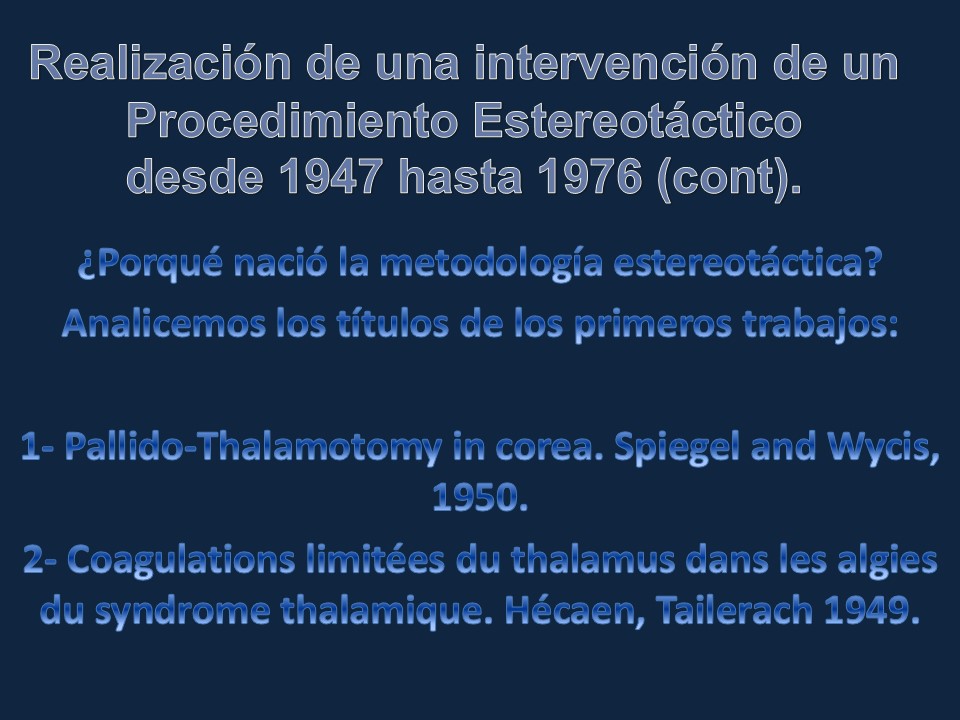

Metodología Estereotáctica o Estereotaxia

Dr. Guillermo Larrarte